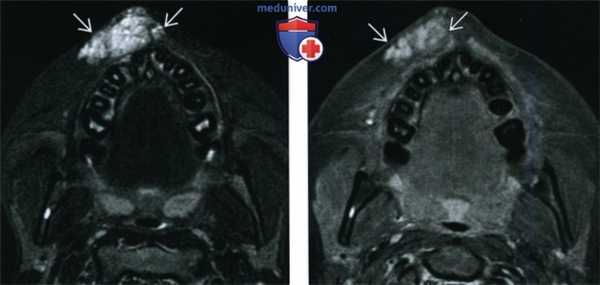

(Слева) На МР Т1ВИ в сагиттальной проекции в корне языка визуализируется врожденная киста валлекулы с ровными краями, содержимое которой имеет сигнал, характерный для жидкости.

(Справа) На МР Т2ВИ в корональной проекции у этого же пациента в передних отделах ротоглотки визуализируется валлекулярная киста с неровным контуром и сигналом, типичным для жидкости.